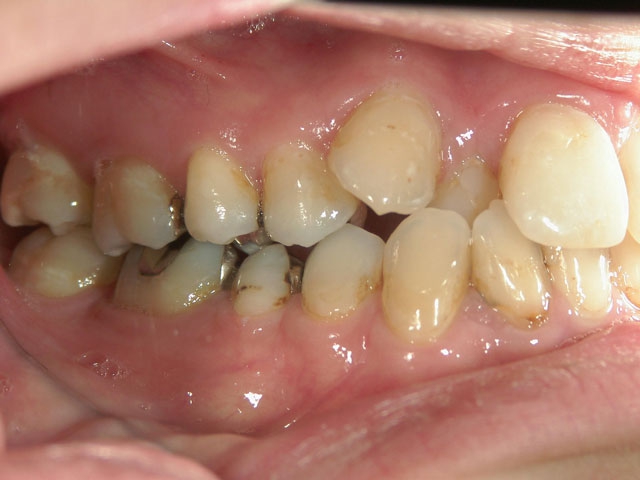

矯正歯科 治療前 外科手術併用(コルチコトミー)、非抜歯

no.7_6967_治療前_右_01.jpgno.7_6967_治療後_正面_01.jpgno.7_6967_治療前_左_01.jpg